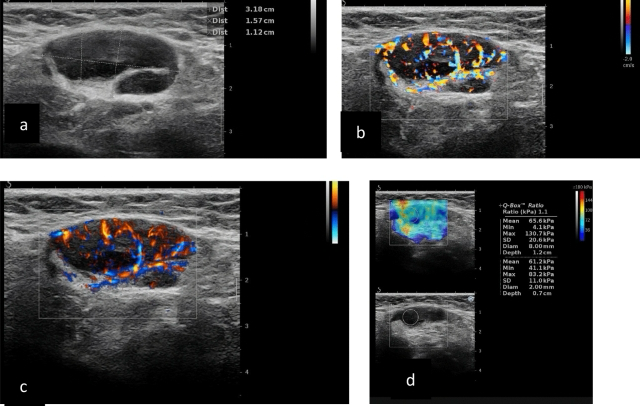

☑️УЗИ лимфоузлов: безопасный, безболезненный и очень информативный метод. Можно оценить размер, форму, структуру и кровоснабжение узла.

Исследования подтверждают высокую диагностическую точность УЗИ в сочетании с допплерографией (оценка наличия сосудов).

Метастатические подмышечные лимфатические узлы при УЗИ